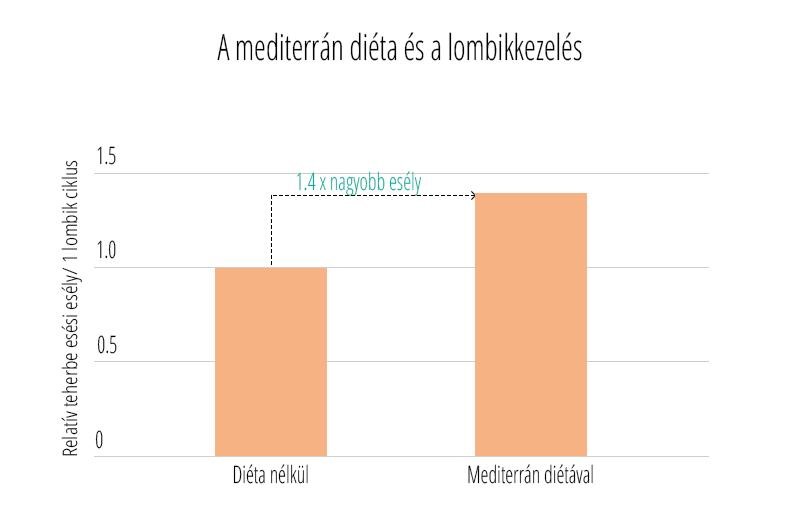

Az edukáció olyan fontos kérdéseket érint, mint: mi számít meddőségnek, mikor érdemes szakemberhez fordulni, hogyan hat az életkor a termékenységre, illetve milyen kockázatot jelentenek a szexuális úton terjedő fertőzések. Az iránymutatás külön kitér a legfontosabb kockázati tényezőkre, mint a dohányzás, a túlzott alkoholfogyasztás, az elhízás vagy éppen az alultápláltság, melyek mind kedvezőtlenül hathatnak a reproduktív egészségre. Ezzel szemben a kiegyensúlyozott, tápanyagokban gazdag étrend, a rendszeres testmozgás, valamint a dohányzás elhagyása bizonyítottan hozzájárulhat a termékenység megőrzéséhez és a későbbi problémák megelőzéséhez.